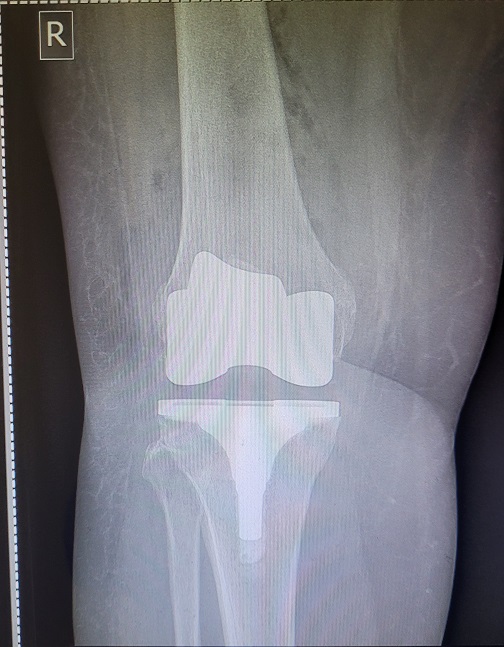

This issue will not apply to all surgeries either. It depends how long your post-op period is AND the degree of immobility required. For example, I’ve had both ankles fused. Same post-op period in both cases. However, with the left ankle I could drive four weeks earlier than with the right ankle and that four weeks, plus an additional, unrelated, hospitalisation, were enough to make what was, in my case, a major difference.

When I had the left ankle done in 2023, by the time I was in a moonboot and on crutches I could drive to the gym and do the weighted back exercises I needed to do to maintain my posterior chain strength. With the right ankle, obviously I couldn’t drive for an additional month. Then, two weeks after I could drive, I was back in hospital for a nasal/sinus infection. Essentially immobile again.